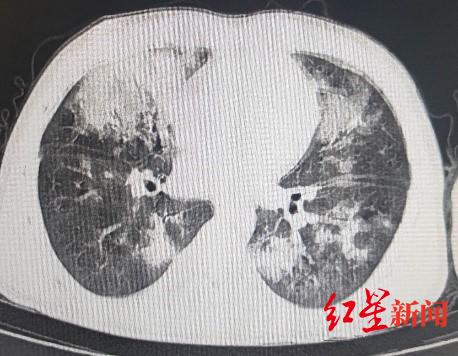

10月11日,红星新闻记者从成都市第三人民医院了解到,8月28日中午13时,小鹏被紧急转送至成都市第三人民医院重症医学科一病区救治。他入院时已呈现严重的休克症状,血压仅65/32mmHg、心率达168次/分、呼吸频率达45次/分、血氧饱和度仅70%、心脏射血分数仅20%……

入院时胸部CT

面对“命悬一线”的少年,张川主任立即率领重症医学科团队联合多学科专家会诊,初步诊断为“暴发性心肌炎,心源性休克,且合并了重症肺炎,重度急性呼吸窘迫综合征,脓毒性心肌病。”